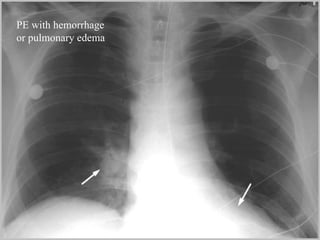

Pulmonary embolism (PE) is a common and potentially fatal condition where blood clots block arteries in the lungs. An estimated 5 million venous thromboses occur annually worldwide, with 10-30% of PE cases correctly diagnosed. Risk factors include older age, cancer, obesity, surgery, trauma, and genetic or acquired hypercoagulable states. Diagnosis involves assessing clinical probability based on symptoms and risk factors, then confirming with tests like D-dimer, chest imaging, ventilation-perfusion scanning, pulmonary angiography, or CT pulmonary angiography. Treatment focuses on anticoagulation to prevent further clotting while allowing natural lysis of existing thrombi.